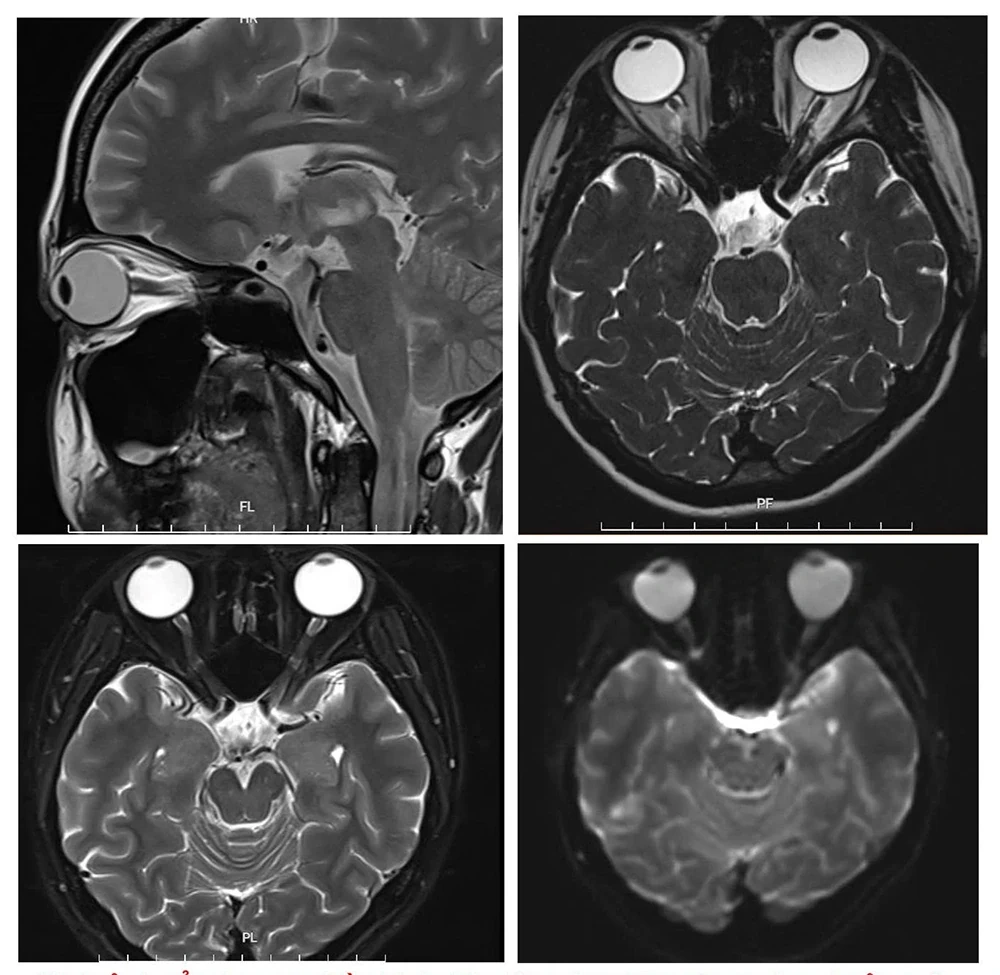

Hình ảnh tổn thương thần kinh thị giác trên phim chụp cộng hưởng từ

Sau 1 tháng ở nhà điều trị theo đơn ngoại trú nhưng không đỡ, gia đình đã đưa người bệnh đến Trung tâm Đột quỵ – Bệnh viện Đa khoa tỉnh Phú Thọ kiểm tra. Tại đây, người bệnh được các bác sĩ thăm khám, làm xét nghiệm máu, chọc dịch não tuỷ, chụp cộng hưởng từ sọ não,... Sau hội chẩn lâm sàng, người bệnh được kết luận bị rối loạn phổ viêm tủy thị thần kinh thể tổn thương thần kinh thị, sàn não thất IV, hành tuỷ lưng bên.